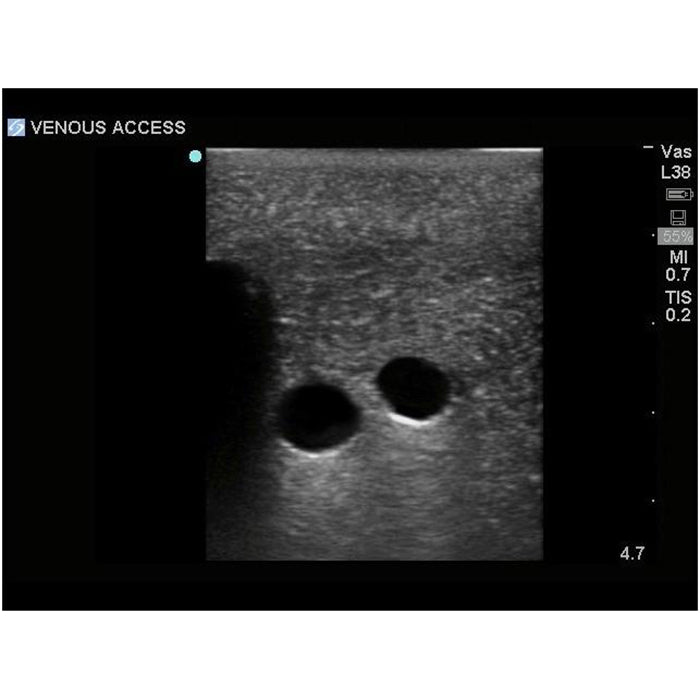

sternal notch. Users can utilize traditional anatomical landmarks for blind insertion techniques, or utilize ultrasound

Brand New! 2nd Generation upper torso ultrasound guided central line placement training model with transparent tissue insert allows users to develop and practice the skills necessary to gain proficiency in using ultrasound to guide central catheter insertions in the internal jugular vein (IJ), subclavian vein, and axillary vein while revealing the venous and arterial vessels as well as accessory boney structures. Developed with the goal of helping clinicians bridge the learning gap by allowing them to see the internal anatomical structures with their eyes as well as with ultrasound imaging, our transparent central line placement tissue offers superb ultrasound hands-on training. Using Blue Phantom proprietary simulated human tissue, this very realistic and ultra-durable transparent central venous access ultrasound training model is excellent for training clinicians in the psychomotor skills associated with ultrasound guided central line placement procedures. These ultrasound imaging skills include; using ultrasound system controls, transducer positioning and movement, recognition of arterial and venous anatomy, using ultrasound to target the appropriate vessels for cannulation, and performing a central venous access procedure.Helps

- Superb ultrasound imaging characteristics

- Tissues match the acoustic characteristics of real human tissue so when you use your ultrasound system on our training models, you experience the same quality you expect from imaging patients in a clinical environment

- Superb ultrasound imaging characteristics

- Tissues match the acoustic characteristics of real human tissue so when you use your ultrasound system on our training models, you experience the same quality you expect from imaging patients in a clinical environment